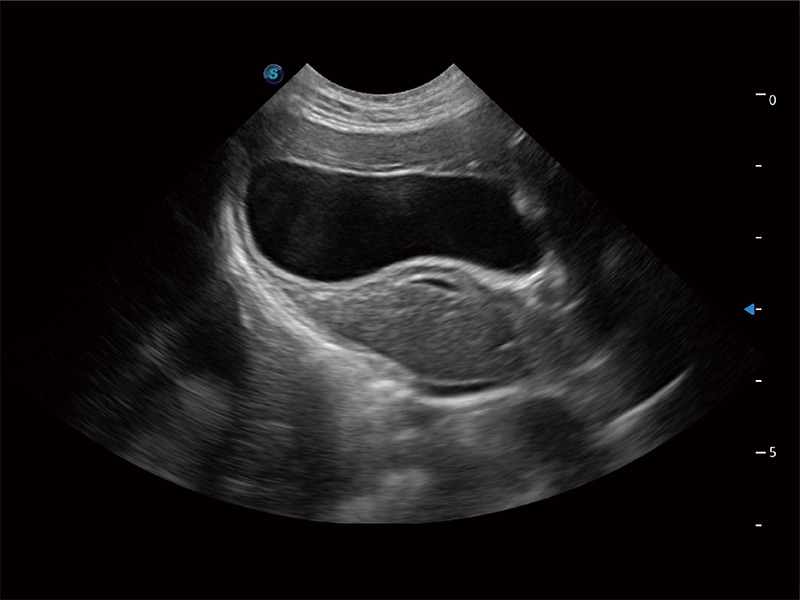

高性能和先進(jìn)的臨床應(yīng)用工具可以為動物醫(yī)生提供臨床信心。ProPet 80 搭載了先進(jìn)的腹部和淺表應(yīng)用工具,幫助醫(yī)生在日常臨床實踐中發(fā)揮前所未有的作用。

ProPet 80 專為動物醫(yī)生設(shè)計,對不同的動物體型和生理結(jié)構(gòu)作出了針對性的優(yōu)化。通過動物影像專用軟件,可滿足個性化的應(yīng)用需求,幫助動物醫(yī)生獲得更精確的診斷數(shù)據(jù)。

為精細(xì)結(jié)構(gòu)及組織邊緣提供高清晰度的圖像和更大的成像視野。幫助減輕醫(yī)生的用眼疲勞,快速精準(zhǔn)獲得測量的數(shù)據(jù)。